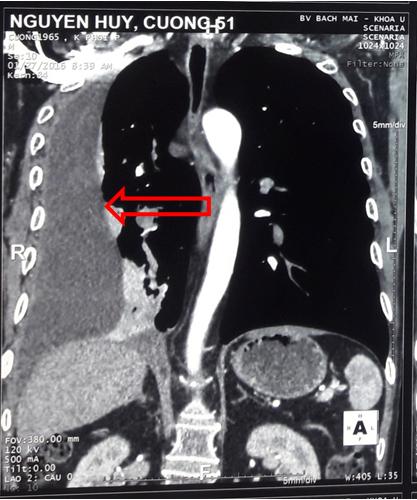

-       Chụp cắt lớp vi tính lồng ngực sau 1 đợt hóa trị phác đồ IP: Hình ảnh tràn dịch màng phổi phải, số lượng nhiều.

Hình 5: Hình ảnh chụp cắt lớp vi tính ngực sau điều trị hóa chất IP 1 chu kỳ: tràn dịch màng phổi phải số lượng nhiều (mũi tên đỏ)